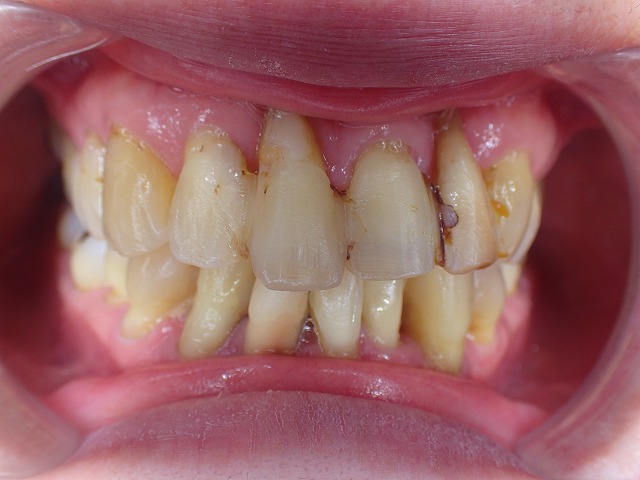

歯がグラグラでも、長期に歯を残す

歯周病で歯の固定

この状態でも歯を抜去せずに

10年以上維持しています。